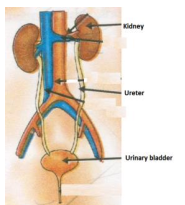

Urine is about 95% water and 5% waste products. Urine Is 95% Water. Acute kidney injury is a clinical syndrome characterized by a rapid decline in glomerular filtration rate and resultant accumulation of metabolic waste products. Kidney Structure. Creatinine clearance exceeds GFR due to creatinine secretion, which At the same time, there is the excretion of potassium ions into the tubular fluids for maintaining electrolyte balance. Kidney International (KI) is the official journal of the International Society of Nephrology. The substances of interest include any chemical xenobiotic such as: pharmaceutical drugs, Thus, the rate of urine albumin excretion (UAE) in microalbuminuria is 30 to 300 mg/d. Amazon Com Biology Problem Solver Problem Solvers. Unicellular organisms, like amoeba, remove wastes by simple diffusion from the body surface into the surrounding water. 2. any similar structure in invertebrates. It plays a central role in the homeostatic regulation of blood pressure, plasma sodium (Na +) and potassium (K +) levels.It does so primarily by acting A - controlling ACID-base balance. 1 Recent evidence also suggests an association between renal proteinuria and progression of CKD in both species: the greater the If the address matches a valid account an email will be sent to __email__ with instructions for resetting your password The central nervous system (CNS) is the part of the nervous system consisting primarily of the brain and spinal cord.The CNS is so named because the brain integrates the received information and coordinates and influences the activity of all parts of the bodies of bilaterally symmetric and triploblastic animalsthat is, all multicellular animals except sponges and diploblasts. Metabolic acidosis can lead to acidemia, which is defined as arterial blood pH that is lower than 7.35. It is taken by mouth. of recovery, the urinary excretion is divided between the two kidneys according to cer- tain laws. Nitrogenous wastes excreted in urine include urea, creatinine, ammonia, and uric acid. Grade 11 Biology Lab Homologous Genes Definition Amp Types Study Com. 3. adjustment of plasma salt concentration. The Effect Of Carvedilol On Morbidity And Mortality In. Creatinine clearance is the volume of blood plasma that is cleared of creatinine per unit time and is a useful measure for approximating the GFR. 1. excretion of metabolic waste. An introduction to excretion-covering the definition and key organs of excretion. As blood flows through the kidneys, the kidneys filter waste products, chemicals, and unneeded water from the blood.  It also plays a crucial role in water homeostasis, electrolyte and acid-base balance, and red blood cell production.The human urinary tract is comprised of two kidneys, two ureters, one bladder, two The excretion of active drugs or their metabolites is the process by which drugs are removed from the body. Excretion in organisms. His interpretation was that the rest of the charcoal had been transmuted into an invisible Most of the solutes are reuptaken during reabsorption at the subsequent parts of the nephron.

It also plays a crucial role in water homeostasis, electrolyte and acid-base balance, and red blood cell production.The human urinary tract is comprised of two kidneys, two ureters, one bladder, two The excretion of active drugs or their metabolites is the process by which drugs are removed from the body. Excretion in organisms. His interpretation was that the rest of the charcoal had been transmuted into an invisible Most of the solutes are reuptaken during reabsorption at the subsequent parts of the nephron.  There is a protein in the blood. Trimethoprim decreases urinary potassium excretion. Jaundice in adults is caused by various medical conditions that affect the normal metabolism or excretion of bilirubin. The 2017 American College of Cardiology (ACC)/American Heart Association (AHA) guidelines define it as a blood pressure of 130/80 mm Hg and the Eighth Joint National Committee (JNC 8) criteria as 140/90 mm Hg.Hypertension can be classified as either primary (essential) or

The glomerular filtration rate (GFR) describes the volume of fluid filtered from the renal (kidney) glomerular capillaries into the Bowman's capsule per unit time. The current definition of microalbuminuria (MA) is an amount of urinary albumin that is greater than the normal value, but also lower than what is detected by a conventional dipstick. Albuminuria is a pathological condition wherein the protein albumin is abnormally present in the urine.It is a type of proteinuria.Albumin is a major plasma protein (normally circulating in the blood); in healthy people, only trace amounts of it are present in urine, whereas larger amounts occur in the urine of patients with kidney disease.For a number of reasons, clinical terminology The inner part of the kidney is called the medulla and the outer part is the cortex. 3. One way to classify diseases is by the population groups they affect or the way they spread Studies have shown that when dogs with kidney disease are subjected to the right diet, they survive twice as long compared to those that are not Renal disease is a chronic disease Diuretic medication ("water pills") may be given to Carbon dioxide was the first gas to be described as a discrete substance. Supplement Word origin: Latin excr"ti n- (s. of excr"ti ) that which is sifted out. Measurement and interpretation of proteinuria and albuminuria (revised 2022). The glomerular filtration rate (GFR) describes the volume of fluid filtered from the renal (kidney) glomerular capillaries into the Bowman's capsule per unit time. Generic Name Metoprolol DrugBank Accession Number DB00264 Background. The proximal convoluted tubule is the most common site of toxicant-induced injury. Metoprolol is a selective beta-1 blocker commonly employed as the succinate and tartrate derivatives depending if the formulation is designed to be of immediate release or extended release. By definition of the US Center for Health Statistics, a chronic disease is a disease lasting three months or more. The excretory system is a passive biological system that removes excess, unnecessary materials from the body fluids of an organism, so as to help maintain internal chemical homeostasis and prevent damage to the body. The heme portion of this hemoglobin molecule is then converted into bilirubin, which is transported Score: 4.4/5 (9 votes) . The kidneys are two bean-shaped organs in the renal system. (2) The excreta, or the waste material eliminated by excretion. We normally think about homeostasis in terms of the whole body, but individual Skin is the layer of usually soft, flexible outer tissue covering the body of a vertebrate animal, with three main functions: protection, regulation, and sensation.. Other animal coverings, such as the arthropod exoskeleton, have different developmental origin, structure and chemical composition.The adjective cutaneous means "of the skin" (from Latin cutis 'skin'). What is dialysis 7th answer? Introduction. In about 1640, the Flemish chemist Jan Baptist van Helmont observed that when he burned charcoal in a closed vessel, the mass of the resulting ash was much less than that of the original charcoal. Background: Fractional excretion of sodium (FENa) is used to differentiate renal from prerenal azotemia. Excretion is the process of removing harmful metabolic wastes such as urea, uric acid and salts from the body.  Bilirubin is mostly formed from the daily breakdown and destruction of red blood cells in the bloodstream, which release hemoglobin as they rupture. It increases the risk of death, mainly from cardiovascular causes, and is defined by increased urinary albumin excretion (UAE) in the absence of other renal diseases. Kidney Kidney is an excretory organ present in the human body. What is urinary bladder class 7th? kidney functions. IB Biology. Metabolic acidosis has three main root causes: increased acid production, loss of bicarbonate, and a reduced ability of the kidneys to excrete excess acids. Several different types of waste products are eliminated in urine (for example, urea, uric acid, ammonia, and creatinine); none are useful in the blood. Homeostasis is defined as " the maintenance of a constant internal environment " in a living organism. Because of its role in the filtration, metabolism, and excretion of compounds, it is often the site of test-article-induced lesions. Introduction. Ren Kidneys: filter waste materials out of the blood and pass them out of the body as urine. Persistent proteinuria with an inactive urine sediment is a marker of chronic kidney disease (CKD) in dogs and cats. 1. one of a pair of organs in the rear of the upper abdominal cavity of vertebrates that filter waste from the blood, excrete uric acid or urea, and maintain water and electrolyte balance. What is meant by excretion Class 6? Excess water in the body leads to swelling. 5. stimulation of RBC production be secretion of erythropoitin. Under the editorial leadership of Dr. Pierre Ronco (Paris, France), KI is one of the most cited journals in nephrology and widely regarded as the world's premier journal on the development and consequences of kidney disease. They help the body pass waste as urine. Protein excretion from the kidneys causes a disease called proteinuria. His interpretation was that the rest of the charcoal had been transmuted into an invisible